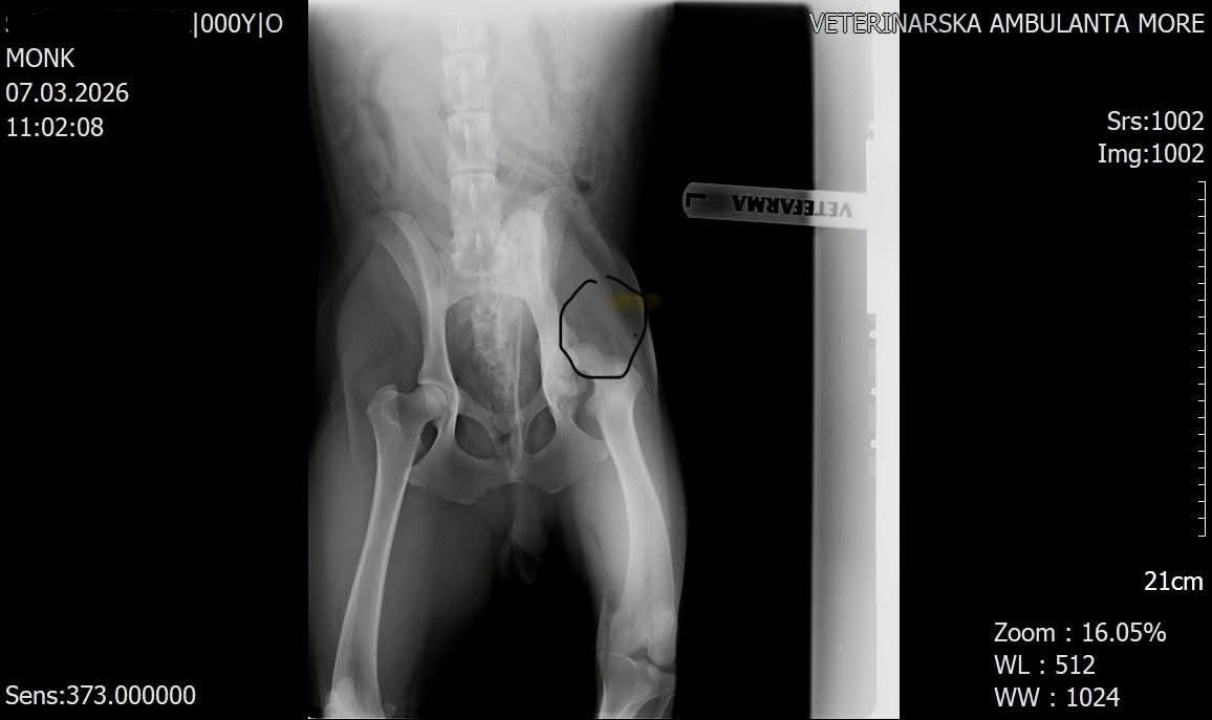

Mora na operaciju kuka

Šibenske šape uputile su apel građanima za pomoć u prikupljanju sredstava za operaciju mladog psa Monka, koji zbog stare ozljede kuka mora na zahvat kako bi mogao normalno hodati i živjeti bez bolova.